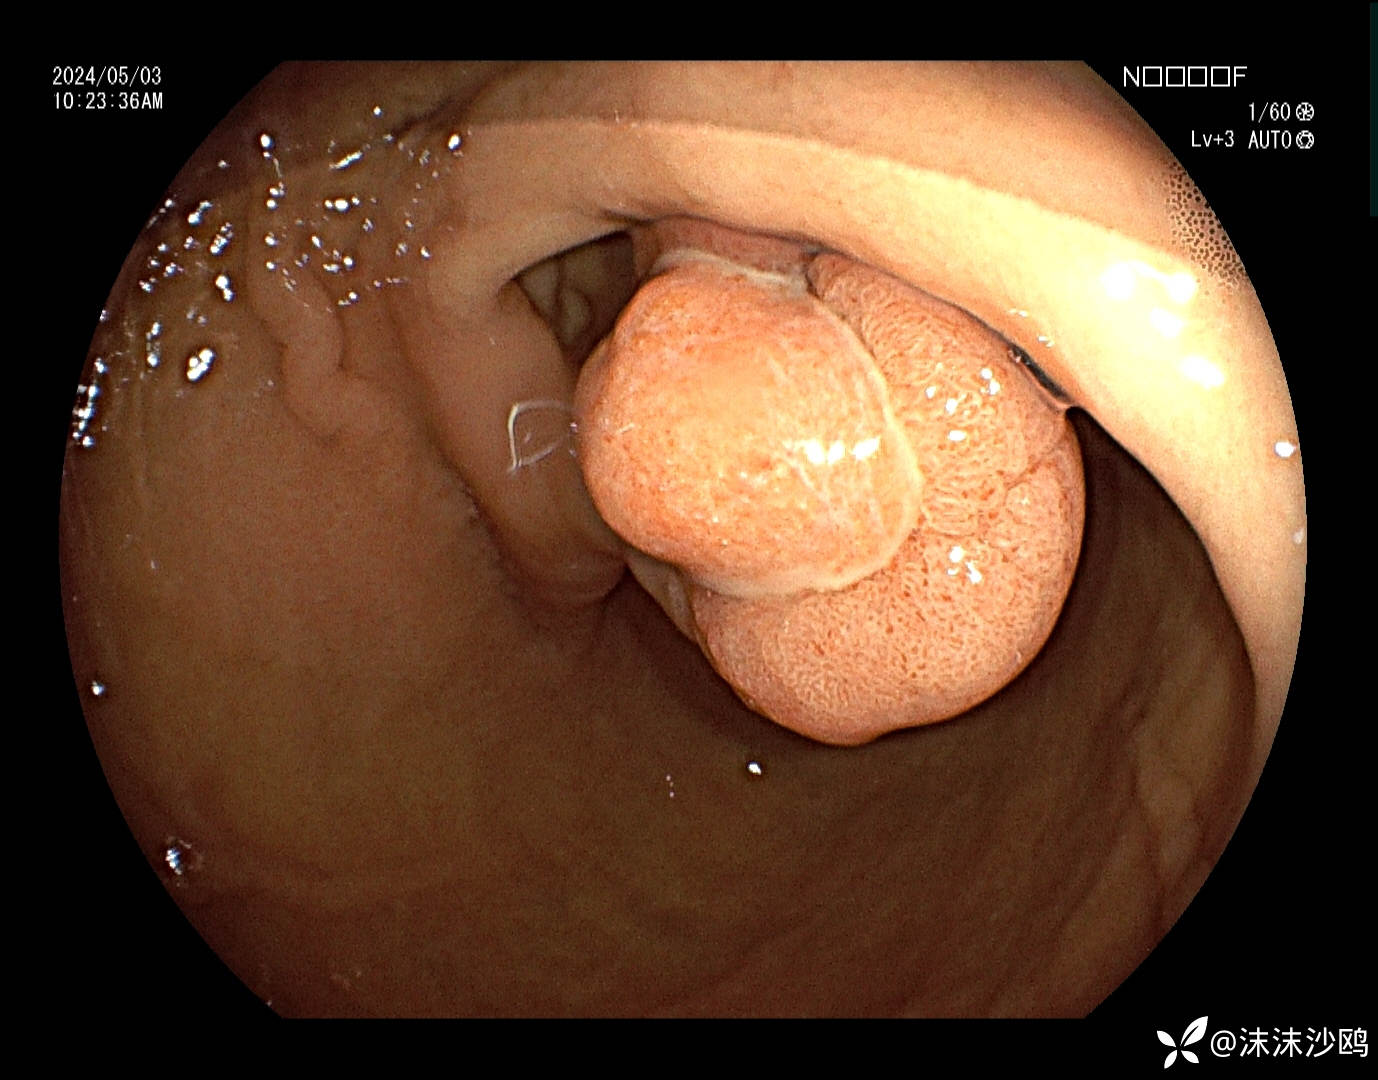

窦体交界近胃角前壁见一较大带蒂隆起性病灶,头端大小直径约2.5cm可见分叶结构,中央隆起跟边缘隆起的表面结构明显不同且有分界,沿分界线走向可见溃疡覆白苔。大致看上去就像一颗水煮蛋剥掉一部分蛋清露出蛋黄的感觉。

蒂部直径约1cm,凹陷见连续性溃疡,局部可见类似红色再生上皮?

倒镜病灶背面